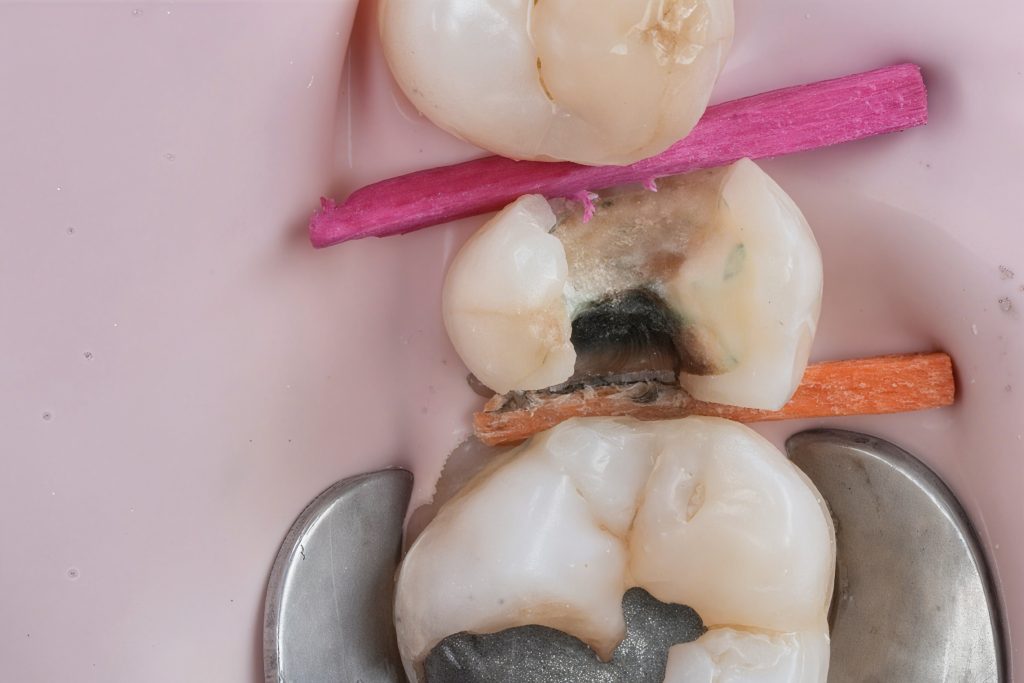

2. Caries Removal & Margin Management

Defective composite and caries were removed in a controlled manner preserving sound enamel walls. Teflon floss ties and wooden wedges used for separation and gingival retraction (Fig 3–6).

- Initial caries exposure and removal

- Proximal clearance and wedge placement